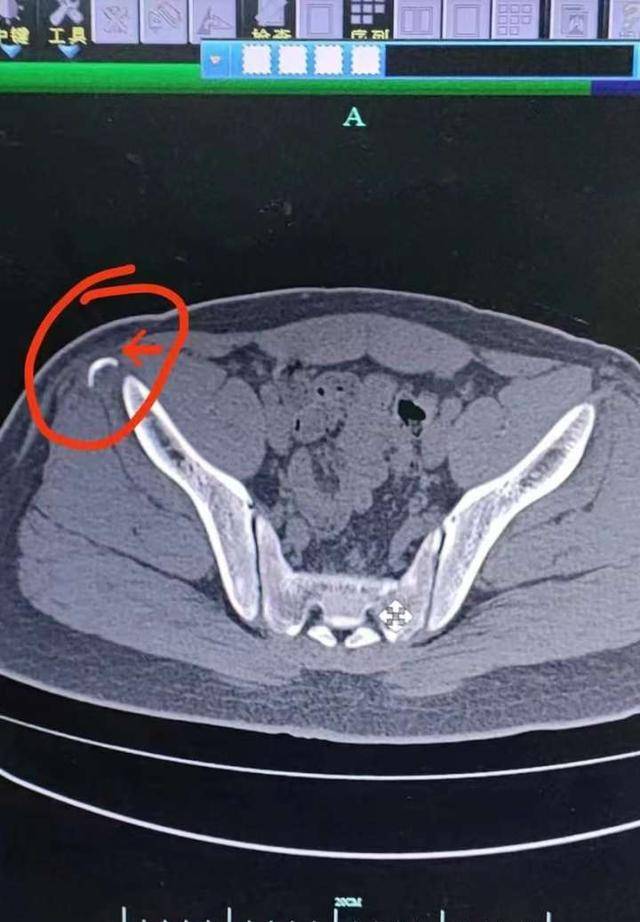

急诊外科医生在查体后发现,小宋的右髂部有些肿胀,右髋的屈伸活动部分

查体 辅查 检查:右髂棘处肿胀,压痛,右大腿活动受限.